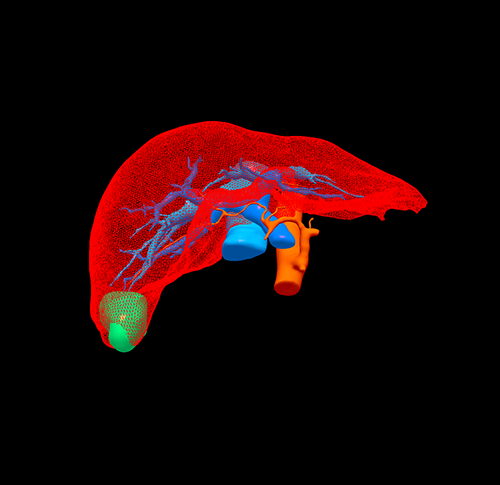

S6肝癌--腹腔镜S6部分切除